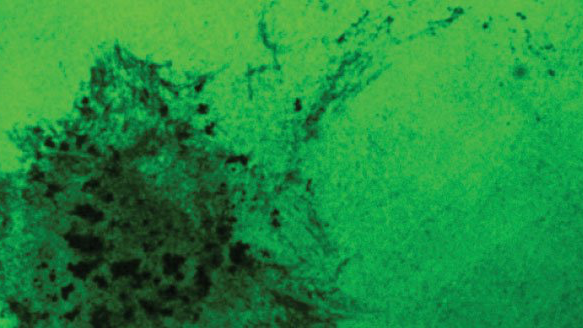

Los investigadores encontraron que el lazo de la respuesta inmune produjo en un aumento de las estructuras invasoras conocidas como "invadapodia", utilizadas por las células cancerosas par invadir y metastatizar.